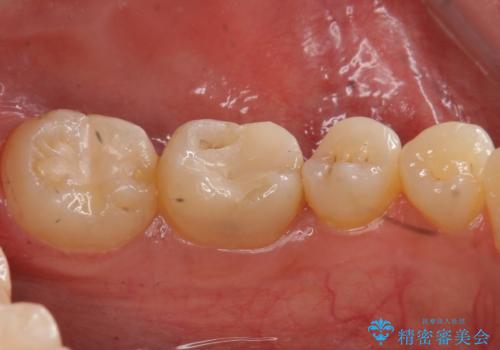

写真・レントゲン画像からもわかる通り、適合の良いクラウンを入れることができました。

- 右下6 仮歯+セラミッククラウン 11000円+110000円 費用は治療当時の料金となります